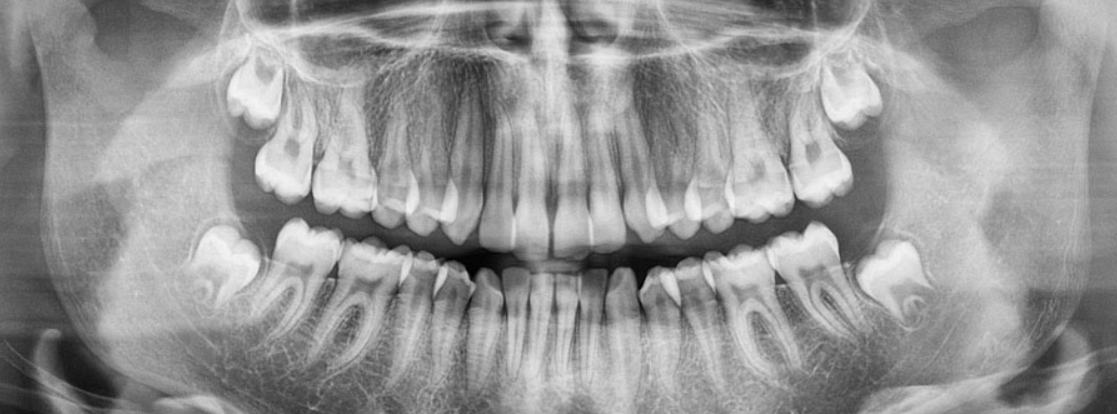

2014 har vi investerat i högupplösta bildsensorer med den senaste tekniken. Vi har möjlighet att ta helkäksbilder med en speciell röntgenapparat som heter ortopantomograf, OPG. Dessa bilder har stor betydelse vid planering av operationer i samband med implantatbehandlingar, uttagning av visdomständer, tandreglering samt vid kontroll av käkar och tänder där ”vanliga” bilder inte räcker till.